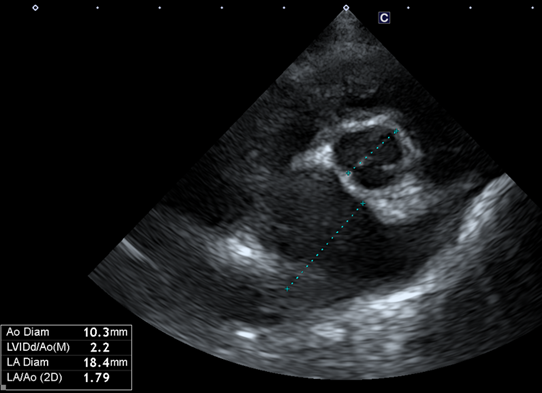

심장 초음파 보겠습니다

판막의 심한 변성과 Prolapse가 존재합니다.(화살표 모양)

좌심방의 크기를 나타내는 LA:AO는 1.79가 나왔습니다(정상은 1:1입니다)

좌심방의 압력을 간접적으로 나타내는 E vel은 많이 낮아졌습니다.

(보통 1.5m/s가 넘으면 폐부종이 터진 상황이거나 터지기 직전 상황입니다)